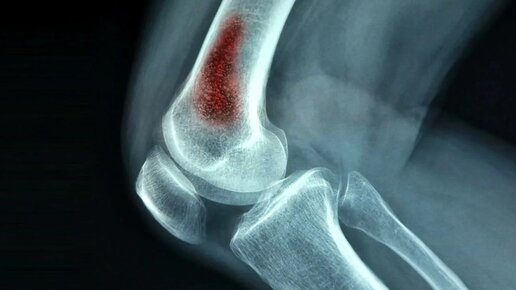

Гнойные заболевания костей и суставов. Хроническая специфическая хирургическая инфекция.